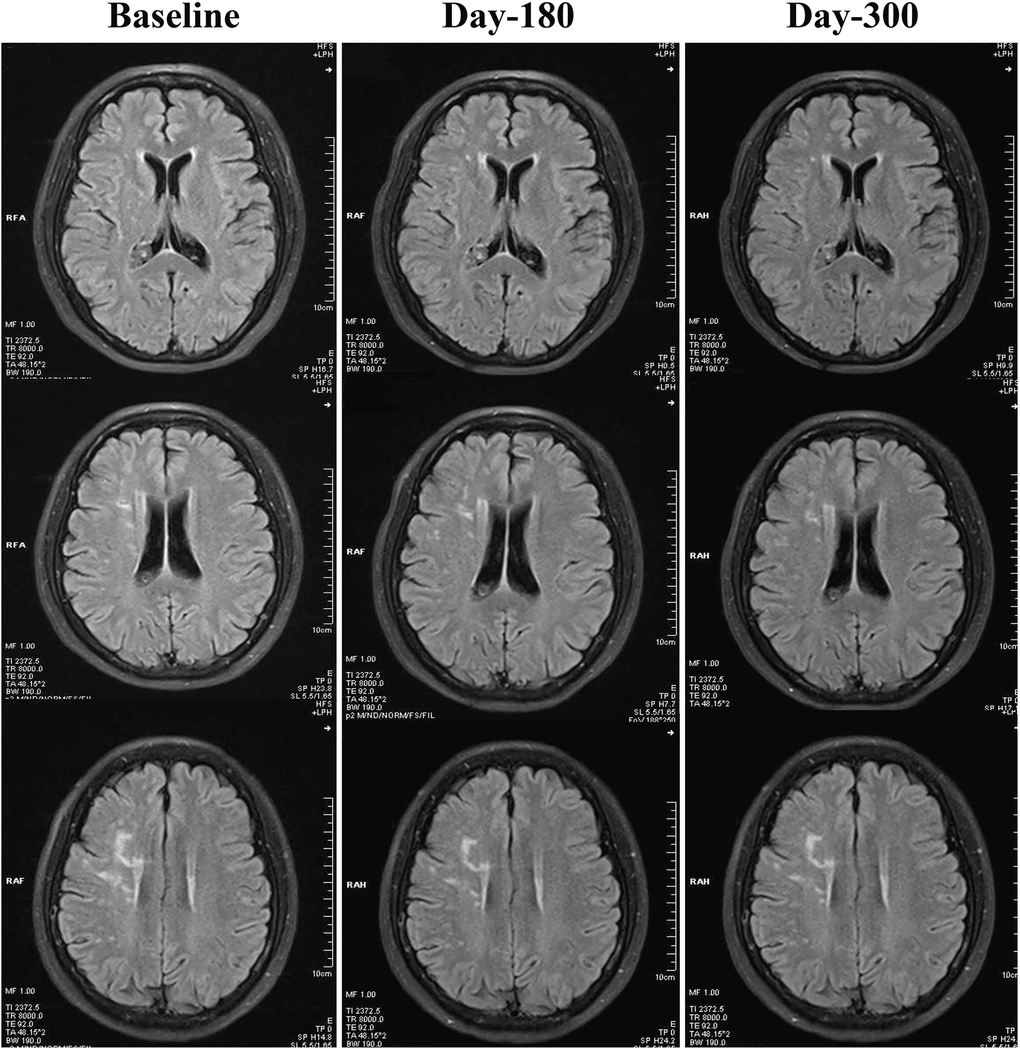

As demonstrated in Table 2, both 180-day (unadjusted p=0.001, adjusted p<0.001) and 300-day (both unadjusted and adjusted p<0.001) RIC treatments significantly decreased scores on the Scheltens scale, as compared with the control group. We also found a statistically significant reduction in the Scheltens scores of the RIC group with time and over days (180-day vs. baseline, p<0.05; 300-day vs. baseline, p<0.01), Figure 1. There was no significant difference in the Scheltens score between the baseline and the 180-day follow-up in the control group, but the score was robustly increased at 300-day (180-day vs. baseline, p>0.05; 300-day vs. baseline, p<0.001), Figure 2.

Figure 1. Changes of WMHs in the RIC group from baseline, day 180 to day 300. Compared with baseline, WMHs in the RIC group were significantly decreased at both day 180 and day 300 follow-ups.